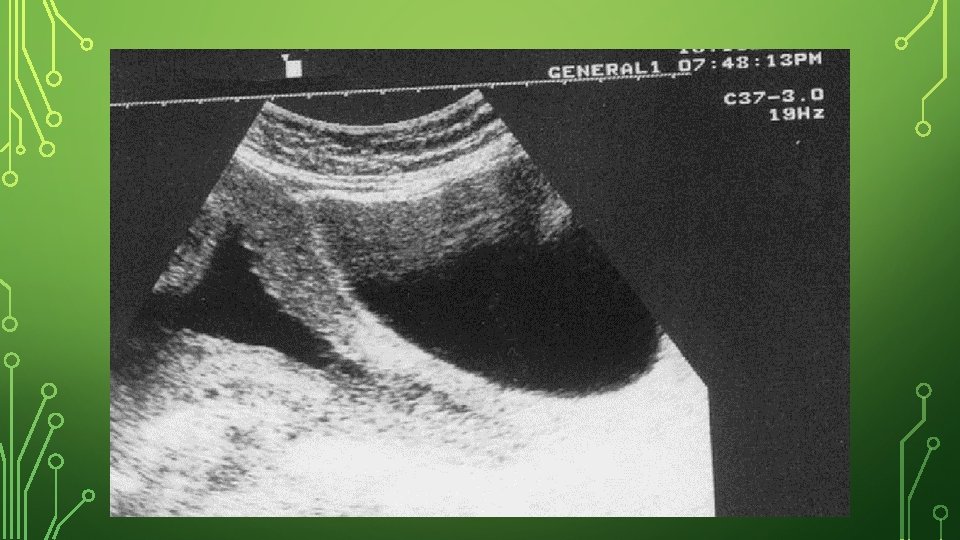

• • • Diagnosis: During pregnancy -Based on an obstetric history of recurrent second- or early thirdtrimester fetal loss with the above criteria mentioned (painless cervical dilation). • -Sudden unexpected rupture of membrane followed by expulsion of the fetus • -Pelvic exam, examine cervix to see if the amniotic sac has begun to protrude through the opening (prolapsed fetal membranes). • - In addition to history, use assessment of cervical length in second trimester to identify cervical shortening using transvaginal ultrasound. However, short cervical length has actually been shown to be a marker of preterm birth rather than cervical incompetence. • Normally, the cervix should be at least 30 mm in length. Cervical incompetence is variably defined. However, a common definition is a cervical length of less than 25 mm at or before 24 weeks of gestational age

-- A normal sagittal view of the cervix shows a “T” shaped endocervical canal vs. deviations such as Y, V, U. Y= initial effacement and subsequent V, U visualized on progressive endocervial change and cervical shortening. TVS assessments in low-risk women to screen for cervical incompetance should not be done routinely. Management should be determined by prior history.